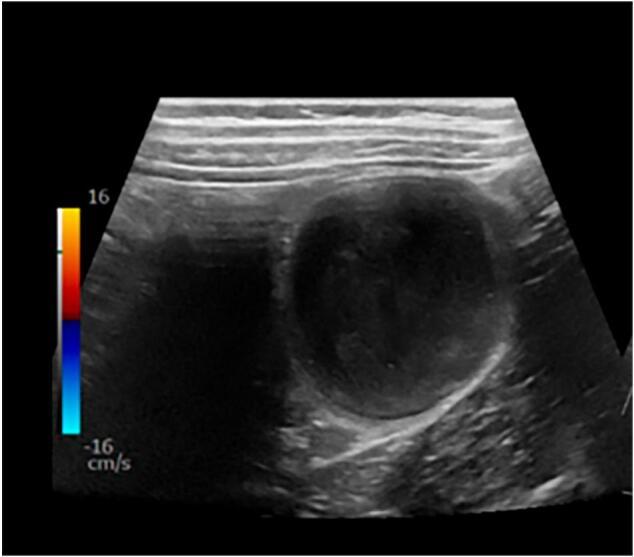

本报告描述了一名11岁男性,因间歇性、时轻时重的腹痛就诊于急诊科(ED),后来被诊断为因结肠神经鞘瘤致套叠点引起的结肠-结肠套叠。最初的腹部超声显示降结肠有一个复杂囊肿。后续的计算机断层扫描证实为结肠-结肠套叠,腔内有实性肿块。随后的结肠镜检查发现脾曲处有一个5厘米宽基底的息肉样肿瘤,内镜下无法切除。进行了左半结肠切除术,切除了6厘米肠段。病理诊断为良性结肠梭形神经鞘瘤。基因筛查无异常,表明是散发性神经鞘瘤,无需额外监测或随访。